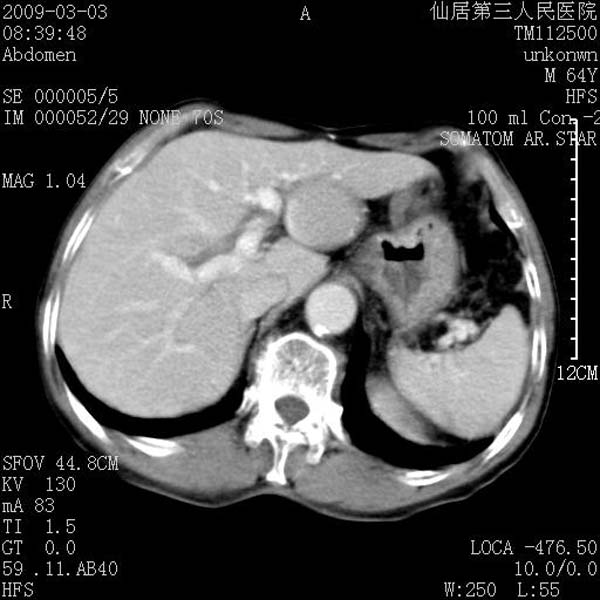

标题: CT18469:男性,64y,体检B超示肝脏低回声肿块,有胃溃疡手术 [打印本页]

患者,男性,64y,体检b超示肝脏低回声肿块,有胃溃疡手术史。

考虑----胃肠道间质瘤可能性大

从平扫及增强的特点来看,支持肝脏腺瘤并出血。

考虑胃间质瘤可能性大。

胃肠道间质瘤!

ct值呢?感觉没强化,象囊性。

考虑肝静脉韧带裂区良性占位性病变(囊肿?)。

考虑肝囊肿并出血可能性大.

考虑高密度囊肿可能性大